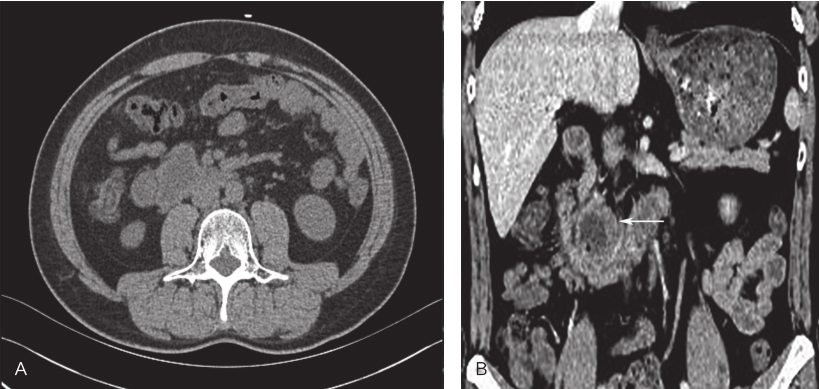

服药10个月后,2018年9月复查全腹增强CT示:十二指肠见等密度肿块影并向外生长,大小约4.9cm×4.0cm,十二指肠GIST病灶较前略缩小,余与前片相仿,无特殊(图4)。患者为求进一步治疗就诊于华中科技大学同济医学院附属协和医院。门诊以“十二指肠GIS全腹增强CT术前治疗后”收治入院。

图4 2018年9月全腹增强CT

2018年12月行上下腹部、盆腔平扫+增强示:十二指肠降部见等低密度肿块影并向外生长,大小约4.9cm×3.5cm(图5),病灶边界清晰,与胰腺钩突、下腔静脉毗邻;中央见不规则液体密度影及新发少许斑点状积气影,肝固有动脉分支向病灶供血,邻近肠系膜根部多发小淋巴结,增强示边缘实性成分可见强化,中心区域低密度影区未见明显强化。余同前。

图5 2018年12月全腹增强CT